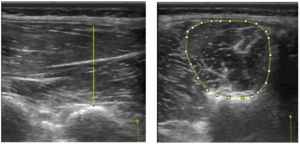

Abb.1: Lateraler (links) und medialer (rechts) Strang der autochthonen Rückenmuskulatur

Abb.2: Segmental angeordnete autochthone Rückenmuskeln